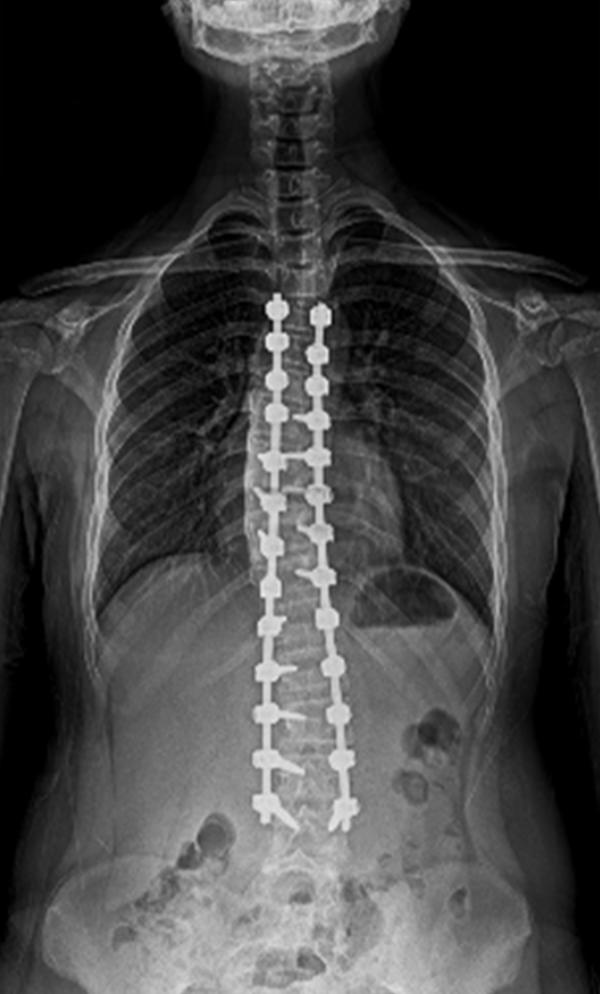

BEYOND RECOVERY : REAL STORIES

Gallery : Before - After